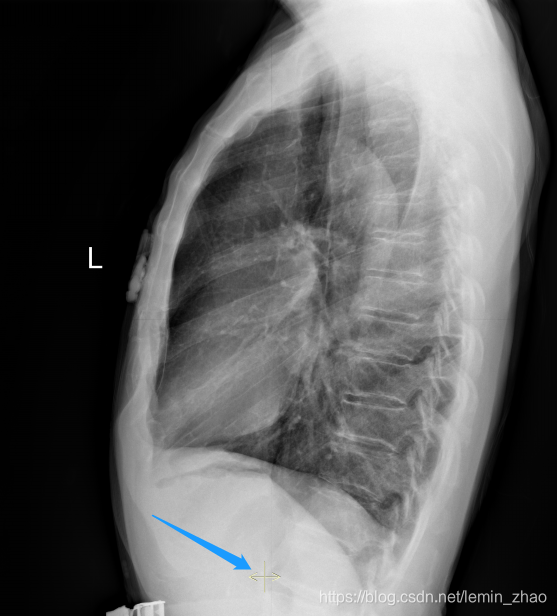

让我们先看看overlay是啥,见下图

蓝色箭头指向的就是overlay层显示的东西